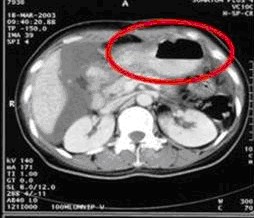

病例1 女,49歲。胃體癌晚期,胃竇增厚強(qiáng)化,與周圍粘連,腹膜增厚,腹腔廣泛轉(zhuǎn)移,伴大量腹水。放/化療失敗,無法手術(shù)。治療方案:腹腔灌注今又生2×1012VP/2次/周,共12周,同時灌注順鉑和5-氟尿嘧啶腹腔,后4…